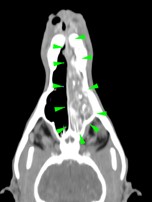

An 11-year-old cocker spaniel was referred to Eastcott Referrals for a chronic nasal discharge and soft tissue swelling in the dorsal aspect of the nose. A CT scan of the head showed a complete obstruction of the left nasal cavity, due to the presence of an amorphous soft tissue mass, extending through the left nasal meatus, left nasal conchae, left sided endoturbinates, left sphenoidal sinus and left frontal sinus (green arrowheads). Bilateral disruption of the turbinates was visible (yellow arrowheads), along with lysis of the left frontomaxillary suture, palatine suture, left rostral portion of the cranium (purple arrowheads) and nasal septum, which was also displaced to the right side